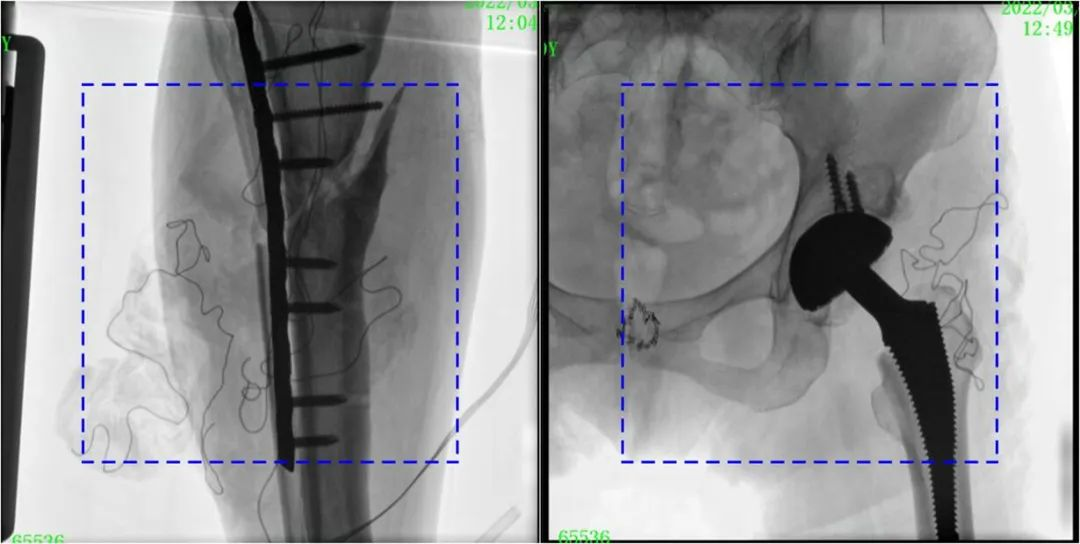

與傳統(tǒng)的21CM×21CM成像尺寸相比,普愛醫(yī)療大平板一體式C形臂具有30CM×30CM更大成像尺寸,能夠一次成像5.5節(jié)椎體,呈現(xiàn)更全面的影像信息,即便是手術(shù)經(jīng)驗(yàn)不豐富的年輕醫(yī)生也能通過圖像迅速判斷椎體節(jié)段、定位手術(shù)部位,避免因?yàn)橐曇安蛔愣斐傻亩啻味ㄎ?、反?fù)曝光,提高效率的同時(shí)避免過量攝入輻射。

普愛醫(yī)療大平板一體式C形臂圖像與傳統(tǒng)圖像對比(藍(lán)色虛線內(nèi)為傳統(tǒng)21CM×21CM平板的成像區(qū)域)